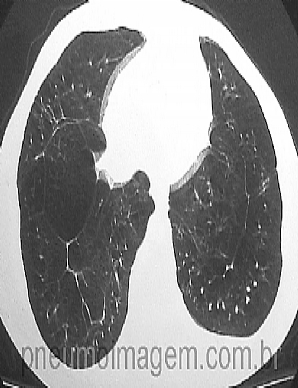

REVISÃO SOBRE DEFICIÊNCIA DE ALFA-1 ANTITRIPSINAA deficiência de alfa-1 antitripsina (A1AT) está relacionada ao desenvolvimento do enfisema pulmonar. Mesmo indivíduos não fumantes, mas portadores desta alteração genética, podem desenvolver a doença. Estima-se que existem entre 200-500 casos de deficiência de A1AT por milhão de pessoas, sendo que muitos são assintomáticos e nunca irão desenvolver enfisema significativo.